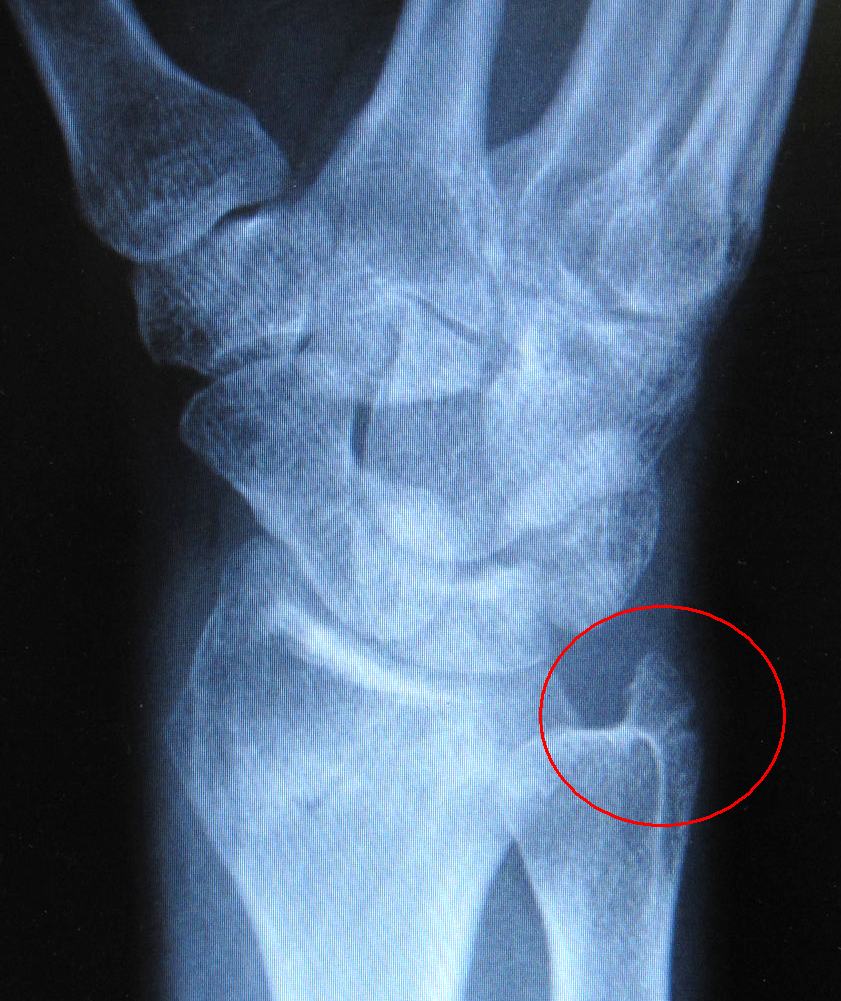

Looking at the X-rays, the doctor said that it had healed up nicely. What I didn't like though was to see that the ulna styloid had folded inwards a bit. I knew the second cast was very tight against there, especially as I turned my wrist downwards to be able to type, it pushed pretty hard against there. The initial X-rays, and the X-rays after the first cast had that styloid in the right place. But this X-ray showed that it was folded inwards a bit. I would assume because of the pressure from the second cast. Surely, that could not have been my fault! :)

When I pointed that out on the X-ray, the doctor said "that's healing pretty good, don't worry". Calcification of bones happens over a much longer period of time, so if you can see any healing in the X-rays at all, that's actually quite a bit of progress already. But what bothers me is that it's folded inwards a bit. I hope this won't cause complications down the road. At the moment, I still have limited range of motion in the wrist (normal after having a cast), so I can't tell if this will be a problem. But knowing what I know now, I would have cut that second cast in half to relieve the pressure immediately. It wasn't a displaced fracture, no bones needed setting, so I didn't need the cast to hold the bones in the right place, I only needed it to avoid messing up the healing. Oh well. Compared to the doctor, I certainly lack perspective on these things, but I think I more than make up for it with obsessiveness! :)